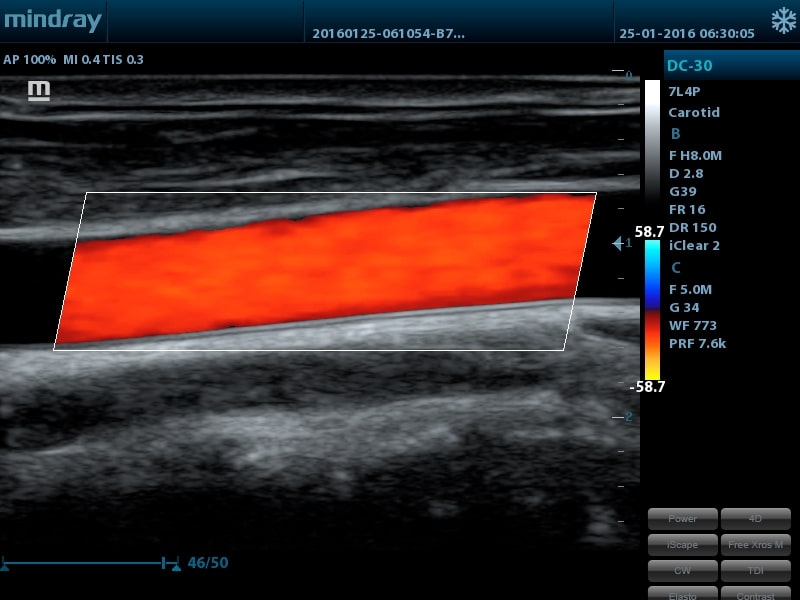

- Auto IMT - автоматическое измерение толщины задней и передней стенок, характеризующие состояние сонной аретерии

- Линейный датчик 7L4P, 3,0 - 13,0 МГц, апертура 38 мм, 128 элементов